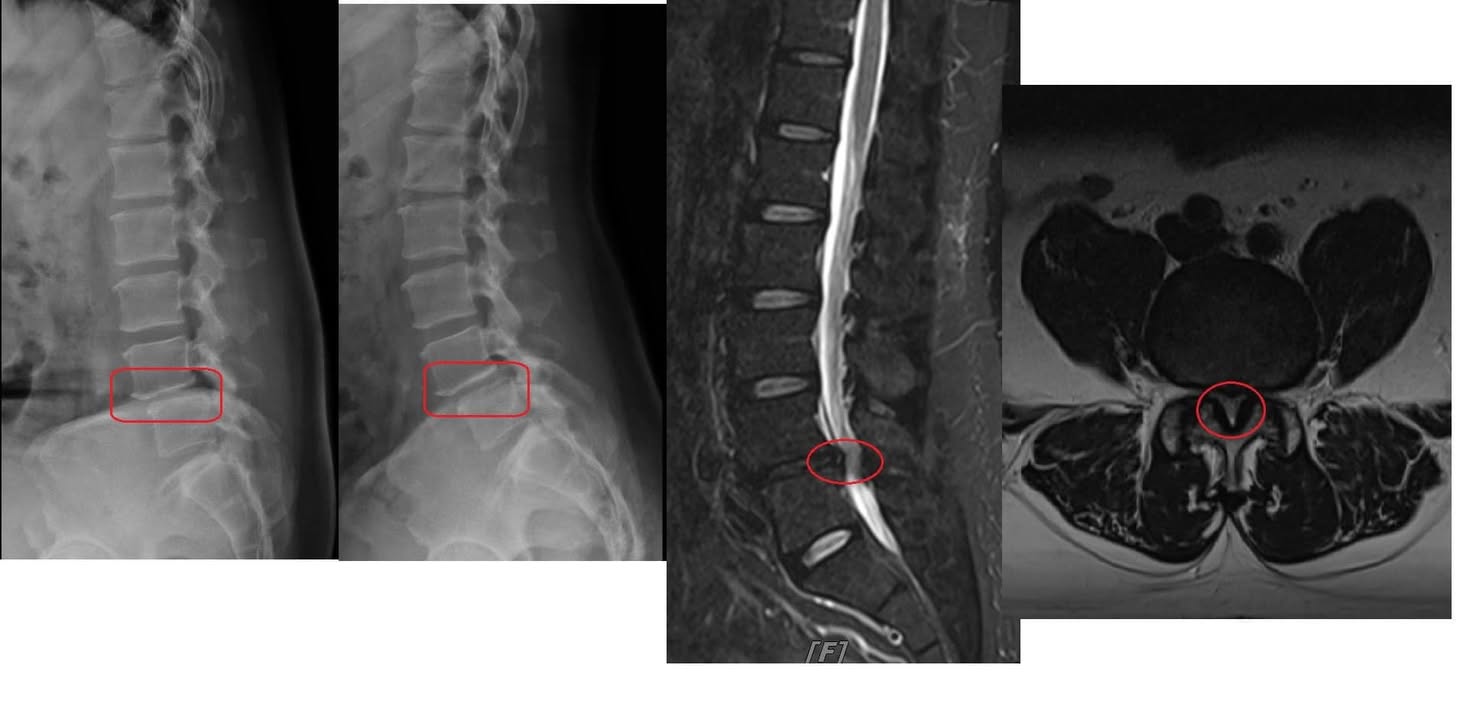

Cervical Spine Treatment Cases 腰椎治療案例 #今天來聊巨大骨刺為何可以吸收回去! #椎間盤突出需要多久才能吸收呢? #馬尾神經症候... 2020.09.08 #典型假性坐骨神經痛 #原來是梨狀肌症候群 #核磁共振排除椎間盤突出 #抽絲剝繭真相大... 2020.08.13 #嚴重椎管狹窄醫案 #感謝台北林大哥熱情見證 #從寸步難行到輕快漫步 #鍛鍊多裂肌的重... 2020.08.12 #椎間盤突出可以吸收回去嗎 #微針治療原理是什麼 #何時一定要接受神外開刀 #一張圖秒... 2020.08.11 #感謝花蓮鄉親林大姐熱情見證 #一分鐘認識椎管狹窄 #原本痛到無法走路打算開刀了 #脊... 2020.08.01 #感謝新莊區林先生熱情見證 #椎間盤突出跟纖維環裂隙的關係 #纖維環破裂突出可以不... 2020.07.28 #逆轉勝又一發case #原本疼痛一年多想說一定要手術治療了 #八週治療後症狀全部消失 #... 2020.07.25 #巨大椎間盤突出一定要開刀嗎 #除了開刀以外的選擇 #感謝台北市吳先生熱情見證 2020.07.24 #腰椎滑脫的疼痛心酸誰人知啊 #一分鐘瞭解腰椎滑脫 #哪一種情況需要積極開刀 #要如何... 2020.07.21 #巨大椎間盤脫垂一定要開刀嗎? #感謝新店林先生熱情見證受訪 #西醫手術有那些選擇... 2020.07.02 #纖維環裂隙AnnularFssures #MRI看起來不嚴重卻嚴重困擾患者 #感謝桃園市蕭先生熱情見... 2020.06.19 #骨刺有可能吸收回去嗎?? #疼痛超過六年的特殊案例探討 #MRI核磁共振前後對比 #感謝... 2020.06.14 #坐骨神經痛一定要開刀嗎 #突出的骨刺真的可以自己吸收嗎 #最新英國醫學期刊BMJ的看... 2020.05.30 #骨刺跟突出髓核有可能吸收回去嗎?? #特殊案例探討 #核磁共振一年後對比 2020.05.29 #從醫以來第一次碰到薦椎Tarlov cyst囊腫#左邊紅色圈圈是個案,右邊是國外案例#腰... 2020.05.23 ← 上一頁 10 11 12 13 14 下一頁 →